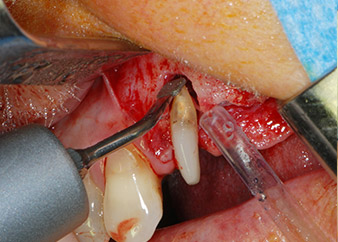

total loss of bone and attachment

Fig. 2 and 3: After raising flaps, one month after endodontic revision and initiation of full-mouth periodontal therapy, the buccal root of tooth 24 showed a total loss of bone and attachment.

However, we maintained our initial plan to retain both teeth as temporary bridge abutments during the six-months osseointegration period of the implants. At reentry, the situation would have to be reassessed. First, in an attempt to manage the endo-perio problem, the remaining root surface was carefully debrided with piezoelectric equipment (Piezomed, W&H, used with the spatula-shaped insert S1, originally designed for erosion of the lateral sinus wall) (Fig. 4).

Then the apex was abraded with the same instrument to remove residual infected apical tissue and to reduce possible accessory root-canal ramifications (apicoectomy) (Fig. 5). A retrograde filling was not necessary because the orthograde filling had just been revised.

periodontium

Fig. 4: To preserve the tooth as a temporary abutment, the periodontium was debrided with piezoelectric equipment …

buccal apex of tooth 24

Fig 5: ... and the buccal apex of tooth 24 was abraded with the same instrument (apicoectomy).